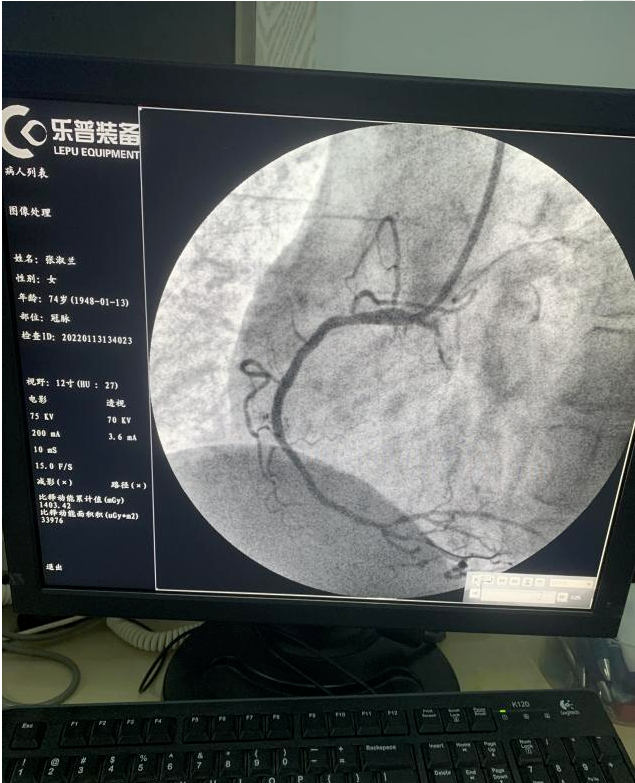

施教授到院后,立即查房评估患者情况,做术前交待病情。得到患者家属同意并签字后,立刻前往导管室。此时,冠脉造影检查显示右冠脉闭塞。

施教授评估血管情况后,凭借着多年丰富的临床经验很快使导丝通过闭塞血管,立即选择合适的预扩球囊开张。

看到了患者最终生命体征恢复,在场所有的人都松了一口气。穿着被汗液浸湿的手术衣,导管室人员相视一笑。但是,所有人都没有放松,手术继续进行。最终,医生成功为心梗患者植入心脏支架。